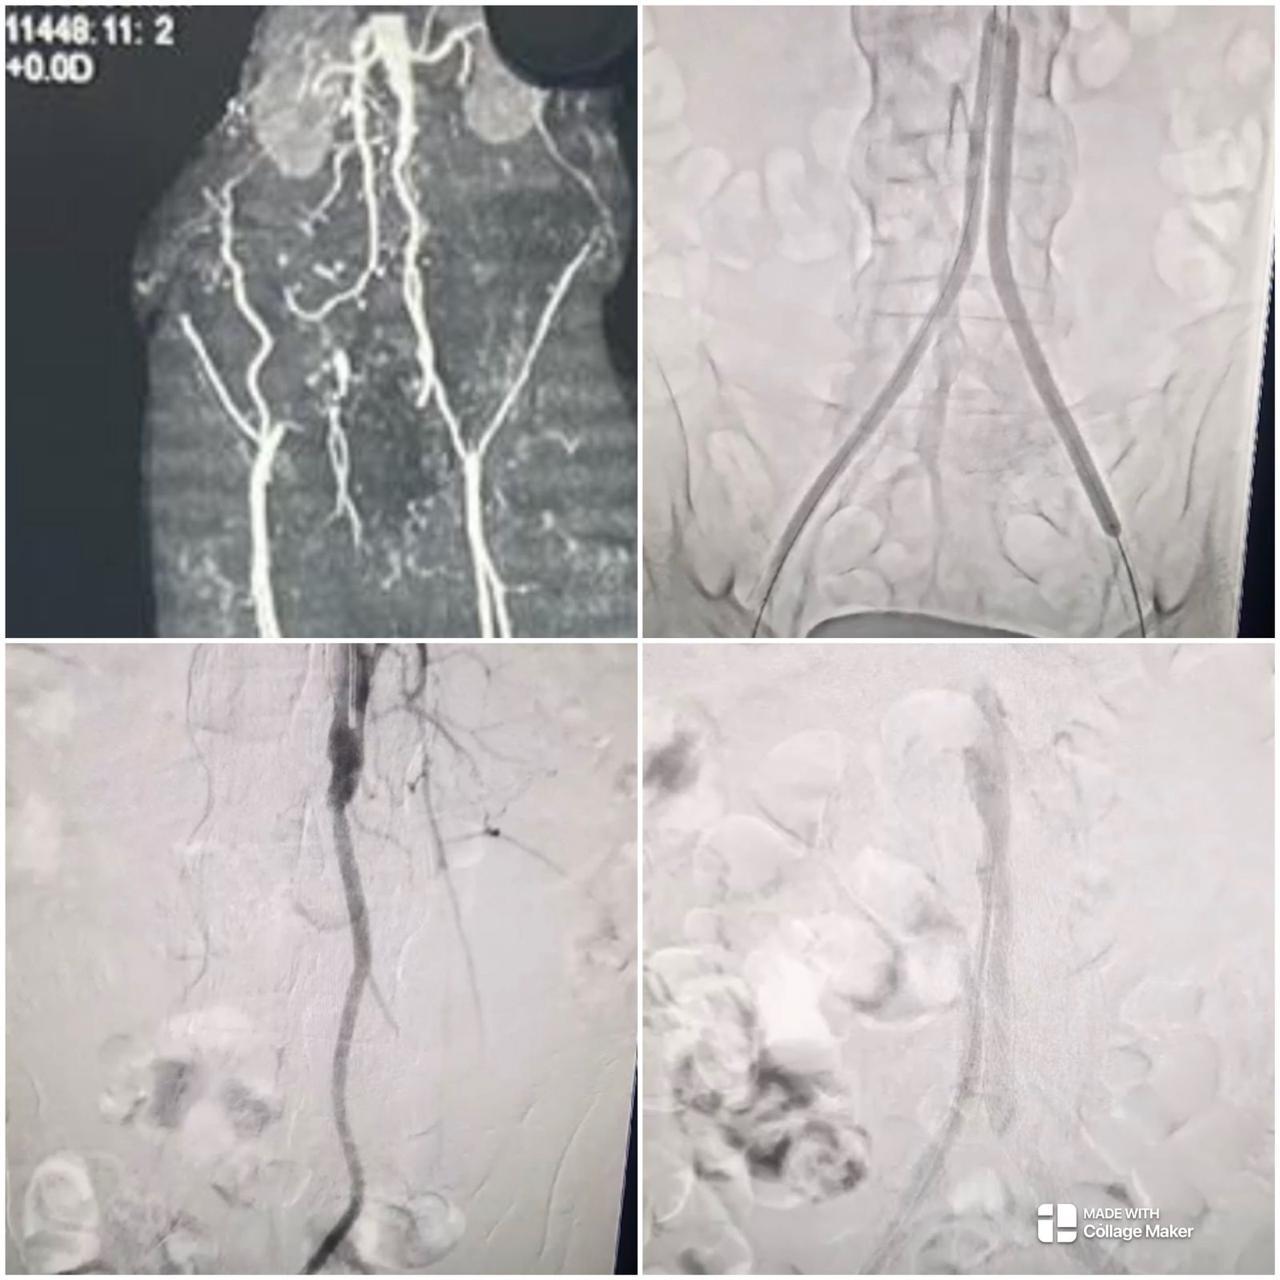

Peripheral Angioplasty procedure at Sarda Vascular Centre Dehradun

Interventional Radiology (IR) uses real-time imaging such as X-ray, ultrasound, CT, or MRI to guide tiny instruments through the body for treatment — without large surgical incisions.